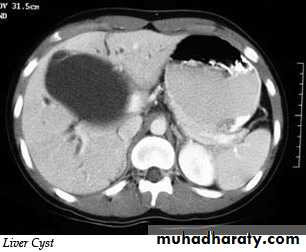

Liver cysts

Simple cysts: may be single or multiple, usually congenital , some are due to infectionMultiple hepatic cysts occur in adult polycystic disease

US features of simple cyst: sharp margin, echofree, with acoustic enhancement

CT features of simple cyst: very well defined margin with water density(HU=0 – 20).

MRI features of simple cyst: low signal on T1 and high signal on T2.

Simple cyst do not show enhancement after IV contrast in CT and MRI